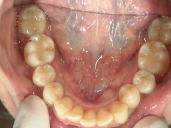

アクアシステム(透明マウスピース矯正)/上顎のみ 症例(1)

28歳 女性 浜松市中区在住  治療期間1年4ヶ月

矯正歯科 治療後 下顎